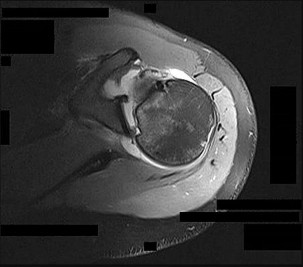

Left shoulder MR imaging results are shown in Figure 19 for a 22-year-old, right-hand-dominant collegiate athlete who reports a 6-month history of weakness in his right arm that first was noticed during weight training. He reports the weakness seems worse now than several months ago. He denies any specific traumatic event, has altered his weight-lifting activities, and has tried over-the-counter ibuprofen without experiencing any benefit. Upon examination of the bilateral upper extremities, there is no appreciable deformity or atrophy. He demonstrates full active shoulder range of motion, and there is no weakness with abduction in the plane of the scapula. Belly press test findings are normal, but there is weakness in external rotation with the arm in adduction. He does not demonstrate anterior apprehension, and there is no instability with load and shift testing. He has normal sensation and pulses to the upper extremity. A standard radiographic shoulder series yields unremarkable results. What is the best surgical option?

This patient’s clinical and MR imaging findings are consistent with a posterior paralabral cyst with compression of the suprascapular nerve, specifically at the spinoglenoid notch. Compression of the suprascapular nerve can occur at either the suprascapular or spinoglenoid notch. Compression of the nerve at the suprascapular notch affects innervation to both the supraspinatus and infraspinatus muscles, resulting in weakness in both shoulder abduction and external rotation. However, compression at the spinoglenoid notch only affects innervation to the infraspinatus muscle, resulting in isolated weakness in external rotation.

Compression at the spinoglenoid notch often is seen in overhead athletes, and studies have shown associated posterior labral tears (Piatt and associates). Several studies have addressed nonsurgical and surgical treatment options. The treatment decision should focus on the underlying cause (Martin and associates)—in this patient, the cyst. Nonsurgical treatment in the presence of a known lesion has been associated with a higher failure rate than addressing the lesion, which can result in functional improvement (Chen and associates, Cummins and associates). The best response in this scenario is decompression of the cyst at the spinoglenoid notch with possible labral repair.